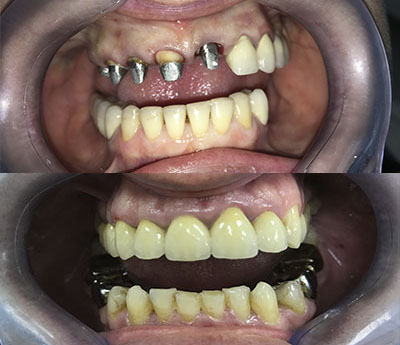

Un tale pezzo protesico ripristina l'integrità delle arcate dentarie. Una protesi mobile correttamente realizzata migliorerà esteticamente i lineamenti del viso del paziente, consentirà il ripristino della funzione masticatoria e migliorerà la fonazione.

Oltre al ripristino estetico della dentatura, il ponte dentale previene le complicazioni che possono derivare dalla mancanza di un dente. Una volta applicato, completerà il normale processo di masticazione e migliorerà la funzione fonetica.

Il sistema Fast&Fixed è un'alternativa immediata. Questa procedura ti permetterà di ritrovare il tuo sorriso in un unico intervento. Il risultato è immediato e recupererai autostima e fiducia in te stesso.